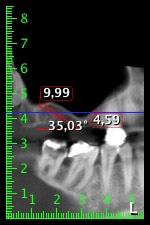

La paziente, 59 anni, presenta un caso di parodontite avanzata e descrive una sensazione di fastidio e scarsa sensibilità gustativa dal primo quadrante in direzione distale. L'esame clinico rivela tasche parodontali generalmente diffuse e un'atrofia ossea molto avanzata nelle regioni 16 e 14. L'esito è confermato dalla radiologia (fig. 1). Non è possibile salvare i denti 16 e 14.

Al fine di pianificare e minimizzare i rischi, circa sei mesi dopo l'estrazione dei denti 16 e 14 viene effettuata una tomografia digitale volumetrica (DVT, Planmeca), la quale conferma chiaramente la mancata rigenerazione ossea nel volume desiderato (da fig. 2 a 7).